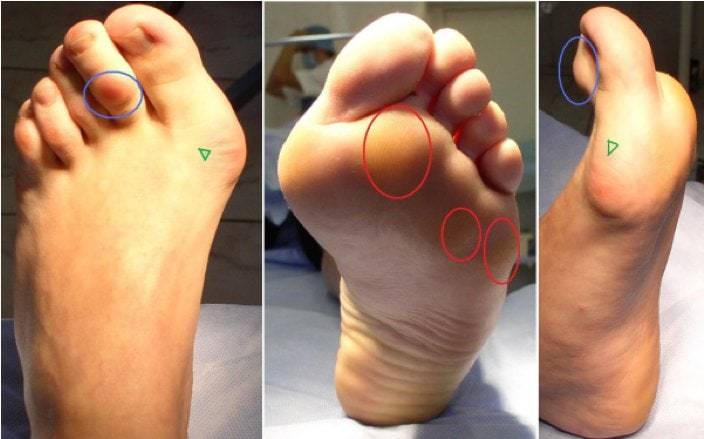

Мы начинаем чувствовать боль в межпальцевых промежутках, потому что нервы зажимаются. У женщин же появляются знаменитые шишки».

Поперечное плоскостопие хорошо видно по расширенному переднему отделу стопы, подсобранным пальцам, отклонению большого пальца внутрь и очень характерным мозолям.

Продольное плоскостопие можно выявить методом сравнения отпечатков стоп с шаблонами. Отпечаток можно сделать дома, намазав стопу краской и наступив на бумагу. Также диагностику стоп сейчас активно проводят во многих ортопедических салонах.

Как и любая биомеханическая проблема, плоскостопие компенсируется организмом за счет укрепления связок и мышц. И при постепенном нарастании нагрузок часто не вызывает симптомов. Поэтому при обнаружении у себя плоскостопия стоит начинать активные действия, если плоскостопие высокой степени (3-4) и сильно выражена гиперпронация. Или если у вас есть следующие симптомы:

- регулярная боль в стопах после бега;

- боль в области пятки или подъема;

- онемение пальцев;

- увеличение опорного сустава большого пальца, боль в нем;

- регулярные боли в голеностопном или коленном суставах после бега.